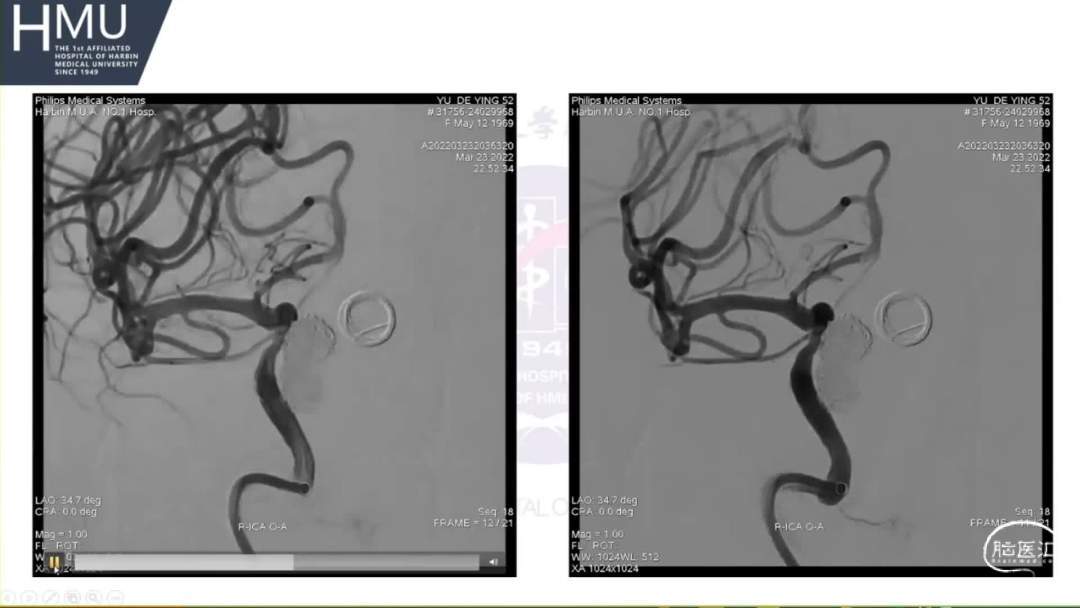

●女,52岁,因“头痛4日,右侧眼脸下垂1日” 入院

入院前4日无诱因出现后枕部头痛,呈针刺样持续性疼痛,入院前1日,出现右眼睑下垂伴眼球胀痛

神清语明,右眼球固定,双侧瞳孔

左:右=2.5mm:5mm,右眼光反射消失,颈强阳性。

21:00覆膜支架置入术

海绵窦段动脉瘤如何导致蛛网膜下腔出血?